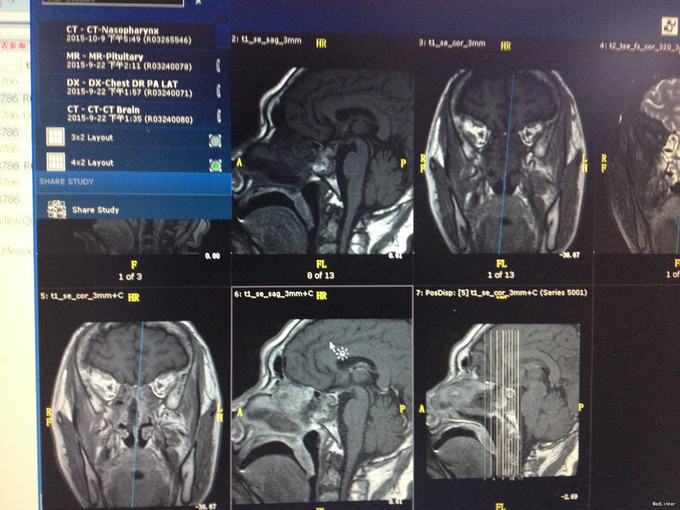

入院查体:口唇增厚,牙列增宽,牙齿稀疏,全身皮肤粗糙、粘膜无黄染及出血点,颈软,左侧甲状腺已切除,可见长约5cm的手术瘢痕,右侧无肿大。 辅助检查, 2015-09-22 08:08 oGTT+胰岛功能: 0分 30分 60分 120分 180分 血糖(mmol/L) 5.67 9.34 11.51 8.16 6.51 胰岛素(mIU/L) 20.77 55.12 148.90 35.43 65.24 C肽(pmmol/L) 1038.472 1957.37 3635.73 3194.84 2571.01 2015-09-22 08:08 葡萄糖抑制试验: 0分 30分 60分 120分 180分 血糖(mmol/L) 5.67 9.34 11.51 8.16 6.51 IGF-1(ng/ml) 1131.00 1196.00 1326.00 1259.00 1002.00 GRH(mIU/L) 32.10 22.80 27.10 23.00 26.00 促性腺激素系列:血清促卵泡刺激素测定FSH35.70mIU/mL,血清促黄体生成素测定LH14.30mIU/mL。血清泌乳素测定PRL257.00mIU/L。尿常规:白细胞每高倍视野JJWBC31.89/HPF,上皮细胞每高倍视野JJEC2.67/HPF,白细胞WBC175.40/uL,上皮细胞 EC14.70/uL。垂体MR平扫+增强:蝶鞍扩大,鞍底下陷,垂体形态饱满,体积增大,垂体右侧T2信号减低,增强后病灶轻度强化,低于正常垂体组织,大小约为1.4x0.8x1.2cm(左右x上下x前后),垂体柄略向左偏移,双侧视交叉略上抬,双侧颈内动脉虹吸部走行正常。诊断意见:鞍区占位性病变,垂体腺瘤可能大,请结合临床。颅脑CT平扫(64排):脑CT未见异常。